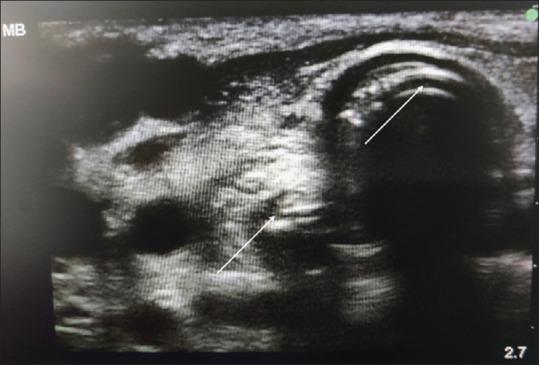

After the detection of novel coronavirus (2019) as the cause of a cluster of pneumonia in Wuhan, China, at the end of 2019, more than 10 million confirmed cases of coronavirus disease 2019 (COVID-19) have been reported around the globe. In the COVID-19 intensive care unit (ICU), the use of stethoscope is minimal for obvious reasons. Shifting of COVID-19 patients out of ICU setup increases the risk of transmission of infection to health-care workers as well as jeopardizes the safety of patients. Hence, diagnostic imaging has emerged as a fundamental component of the current management of COVID-19. Lung ultrasound (LUS) imaging has become a safe bedside imaging alternative that does not expose the patient to radiation and minimizes the risk of contamination. Ultrasound (USG) can be used to scan almost all vital organs (heart, kidney, vascular, brain, etc.) and also help in rapid decision-making regarding the management of COVID-19 patients. In this note, we review the current state of the art of LUS in evaluating pulmonary changes induced by COVID-19. The goal is to identify characteristic sonographic findings most suited for the diagnosis of COVID-19 pneumonia infections as well as to assess the impact of infection on other organs and utilizing the same in the management of COVID patients without compromising on the safety of patient or health-care provider.

2019年末在中国武汉发现新型冠状病毒(2019)是一组肺炎病例的病因后,全球已报告超过1000万例2019冠状病毒病(COVID-19)确诊病例。在COVID-19重症监护病房(ICU),由于显而易见的原因,听诊器的使用极少。将COVID-19患者转出ICU会增加感染传播给医护人员的风险,同时也危及患者安全。因此,诊断成像已成为当前COVID-19管理的一个基本组成部分。肺部超声(LUS)成像已成为一种安全的床旁成像选择,不会使患者暴露于辐射下,并将污染风险降至最低。超声(USG)可用于扫描几乎所有重要器官(心脏、肾脏、血管、大脑等),也有助于对COVID-19患者的管理做出快速决策。在本笔记中,我们回顾了LUS在评估COVID-19引起的肺部变化方面的当前技术水平。目标是确定最适合诊断COVID-19肺炎感染的特征性超声表现,以及评估感染对其他器官的影响,并在不损害患者或医护人员安全的情况下将其用于COVID患者的管理。